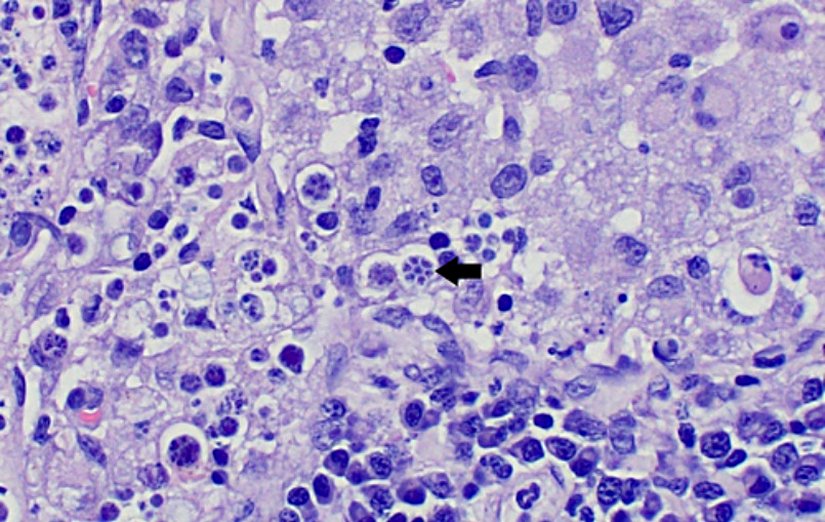

Prototheca, dairesel bir hücre yapısına sahip olup türe ve gelişme evresine göre çapı ve büyüklüğü değişmektedir. Lakin tipik olgun bir Prototheca hücresi 2-30 mikrometre çapa sahip olup ancak ışık mikroskobunda gözlemlenebilen çoğunlukla saydam görünen bir mikroalg genusudur. Mikroskobik muayenesi mutlaka boyama yapılarak gerçekleştirilmelidir.

Prototecha endosporulasyon olarak adlandırılan bir çeşit eşeysiz üreme şekliyle kendi soyunu devam ettirir. Histopatolojik veya sitolojik boyama teknikleri sayesinde bir vejetatif hücre içerisine bulunan birden fazla soyu tespit etmek mümkündür. Bu da mikroskoptaki karakteristik özelliklerinden birisidir.